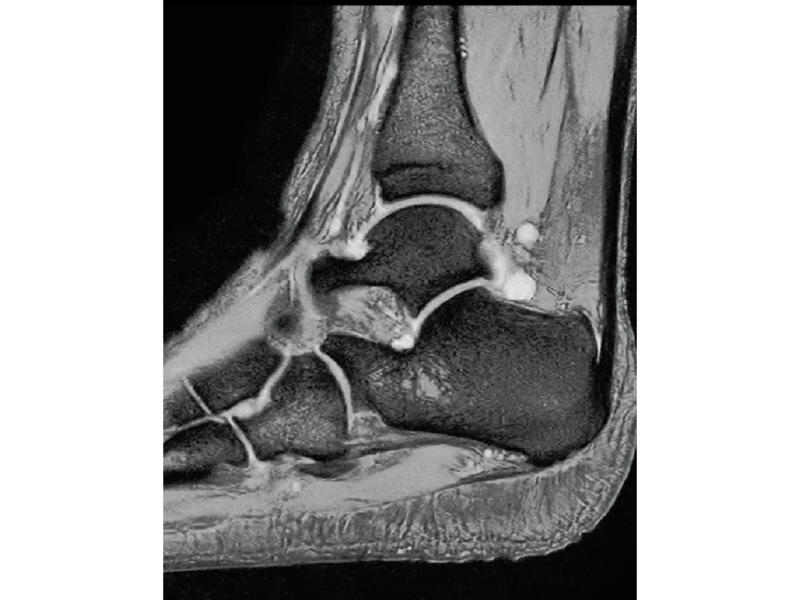

T2*WI Multi Echo,

0.35×0.40×3.0mm, 2:55